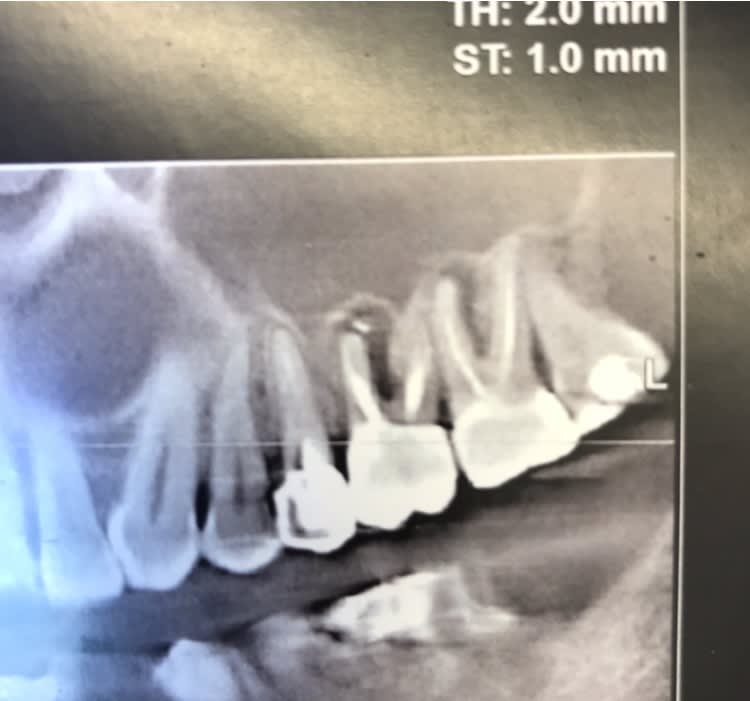

Patiente pas venue depuis trois ans qui revient suite douleur sur 26 prise par un confrere en urgence qui lui dit avoir devitalisé la dent et la patinete revient car toujours douleur et là catastrophe j'enleve le cavit et je comprends la cause des douleurs... mta ou avulsion?

Radio

Sur la radio, tu vois un colossal depassement de pâte en palatin, fais un CBCT et tu en sauras plus.

Mais pour moi, carie juxta-osseuse+depassement inoperable+douleurs= extraction...

le depassement palatin ne m'interpelle pas plus que ça : il y a des quantités de patients qui vivent avec de la pate dans les sinius sans déclencher de pathologies spécifiques et sans comprommettre le mouvement ciliaire

il peut correspondre à un canal accessoire alors pas grave

il peut correspondre à une resorption (potentiellement plus ennuyeux)

simplement surveillance radio tous les 3 mois pour voir si le depassement migre

dans la première hypothèse si le depasst migre laisser apprecier à un ORL le risque d'aspergilose

dans le 2e cas il faut extraire la dent et gerer conjointement le depassement